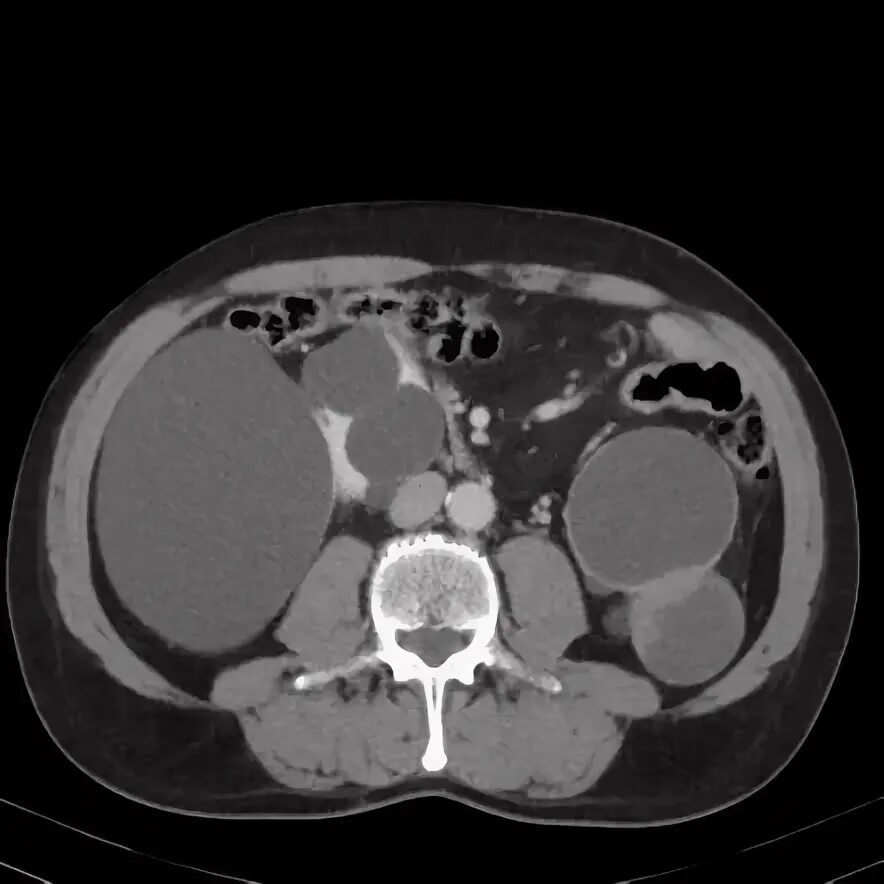

Кисты почек bosniak